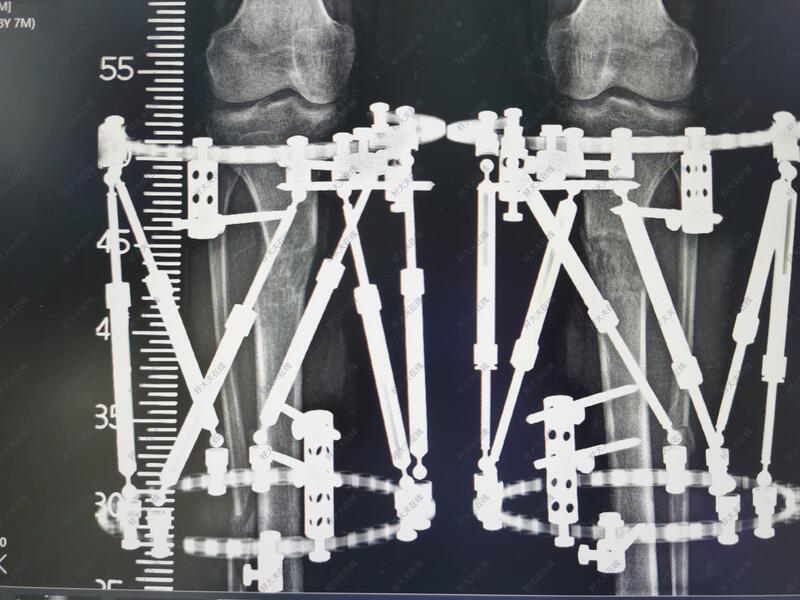

治疗中

六轴空间矫形支架具有调节精准准,病人可以早期负重